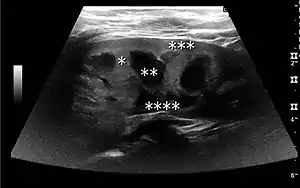

The kidney is divided into parenchyma and renal sinus. The renal sinus is hyperechoic and is composed of calyces, the renal pelvis, fat and the major intrarenal vessels. In the normal kidney, the urinary collecting system in the renal sinus is not visible, but it creates a heteroechoic appearance with the interposed fat and vessels. The parenchyma is more hypoechoic and homogenous and is divided into the outermost cortex and the innermost and slightly less echogenic medullary pyramids. Between the pyramids are the cortical infoldings, called columns of Bertin (Figure 1). In the pediatric patient, it is easier to differentiate the hypoechoic medullar pyramids from the more echogenic peripheral zone of the cortex in the parenchyma rim, as well as the columns of Bertin (Figure 2).[1]

Figure 1. Normal adult kidney. Measurement of kidney length on the US image is illustrated by ‘+’ and a dashed line. *Column of Bertin; ** pyramid; *** cortex; **** sinus.[1]

The length of the adult kidney is normally 10–12 cm, and the right kidney is often slightly longer than the left kidney. The adult kidney size is variable due to the correlation with body height and age; however, normograms for pediatric kidney size are available.[1]

Cortical thickness should be estimated from the base of the pyramid and is generally 7–10 mm. If the pyramids are difficult to differentiate, the parenchymal thickness can be measured instead and should be 15–20 mm (Figure 3). The echogenicity of the cortex decreases with age and is less echogenic than or equal to the liver and spleen at the same depth in individuals older than six months. In neonates and children up to six months of age, the cortex is more echogenic than the liver and spleen when compared at the same depth.[1]